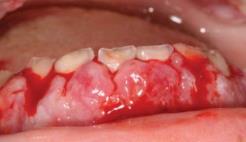

Nem ritka, hogy a leukaemia első tünete a szájnyálkahártyán jelenik meg, igen változatos formában, de elsősorban a gingiván manifesztálódik, mely a leukaemia típusától függően vagy jelentős ínyduzzanat vagy ínyfekély formájában, vagy a kettő kombinációjában manifesztálódik. A duzzadt gingiva soha nem fibroticus, hanem törékeny, hyperaemiás, szivacsszerű és spontán vérzik. A 15.4. táblázat a leukaemiák szájtüneteit mutatja. Néhány esetben a nem túl súlyos ínyhyperplasia az akut myeloid leukaemia első jele, az íny nem hyperplasticus, csak gyulladásmentes mély ínyfekélyek jelennek meg, és az íny spontán vérzik (15.4. ábra (a, b)–15.5. ábra (a, b)).

15.5. ábra. Spontán vérző íny akut leukaemiában